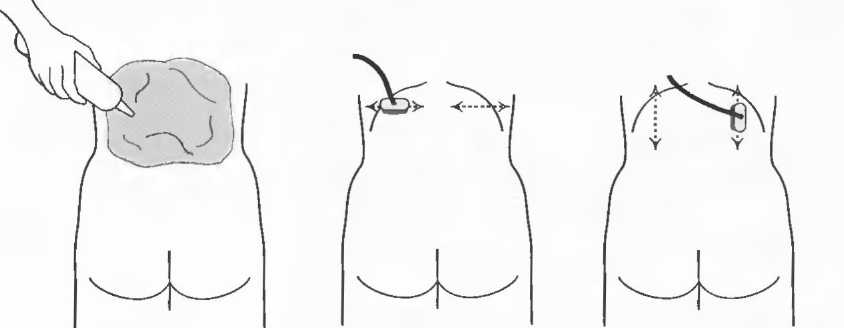

1. Подготовка

Пациент не должен пить и есть в течение 8 ч перед исследованием. Если жидкость необходима для предотвращения дегидратации, можно давать пациенту только воду. При острой симптоматике исследование можно проводить без подготовки. Детям, если позволяют клинические условия, пища и вода не даются в течение 3 ч до исследования.

При более углубленном исследовании, если нет клинических противопоказаний, может быть полезным дополнительный прием воды, особенно при исследовании поджелудочной железы, нижних отделов живота и таза.

2. Положение пациента. Пациент может лежать в удобной позе на спине. Под голову можно положить маленькую подушку, в случае выраженного напряжения передней брюшной стенки подушечку можно поместить также под колени пациента.

Намажьте живот гелем.

Пациенту разрешается дышать спокойно, однако при исследовании отдельных органов требуется задержка дыхания на вдохе.

3. Выбор датчика. Используйте датчик 3,5 МГц для взрослых и датчик 5 МГц для детей и худых взрослых. Предпочтительны конвексные или секторные датчики.